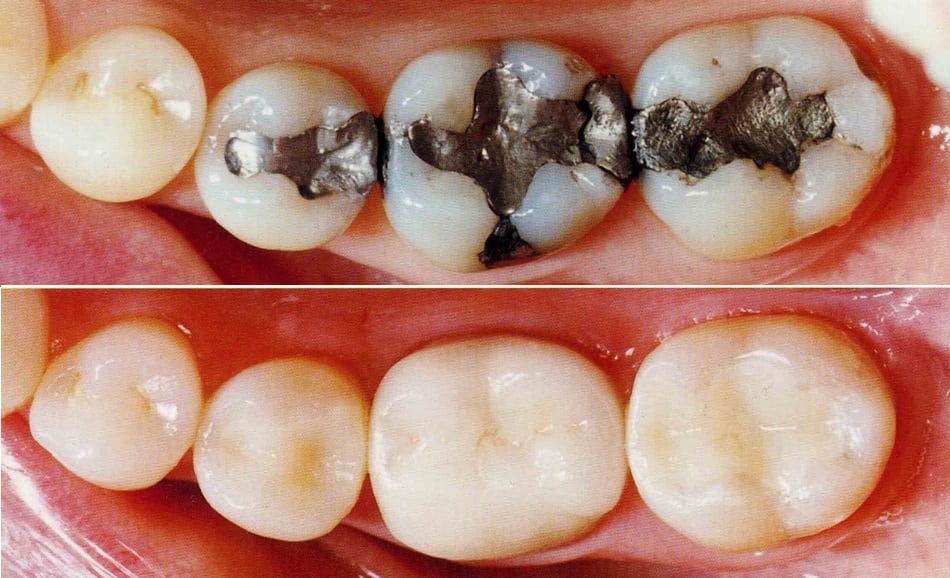

Dr. Jaipal Reddy is an experienced and highly regarded dental surgeon and cosmetic dentist based in Koramangala, Bengaluru. He is the founder and lead dentist at JP Dental Clinic, a well-established dental practice known for comprehensive, patient-centric oral care. Dr. Reddy holds a Bachelor of Dental Surgery (BDS) degree from the Government Dental College and Research Institute, Bangalore, and brings over 25 years of clinical experience in general dentistry, endodontics, and cosmetic dental procedures.